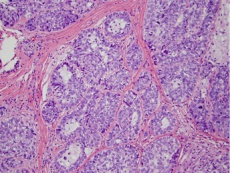

Histopathology

The histopathology varies depending on the differentiation of the tumor. In well differentiated lesions, there is a lobular arrangement and vacuolization of the cytoplasm cells centrally.

Cells present will include sebaceous and undifferentiated cells. There may be variation in nucleus shape and size with high mitotic activity indicated by mitotic figures. Special stains can be used to help distinguish sebaceous carcinoma: oil red-O, Sudan IV, epithelial membrane antigen, Leu-m1 immunostains. [1]

Below are examples of sebaceous carcinoma. The first image shows an eyelid margin with normal sebaceous glands at the inferior margin, the invasive sebaceous carcinoma, and a hair follicle in between. The 2nd and 3rd images are high power images of the carcinoma (with mitotic figures in deep purple) and normal sebaceous glands.